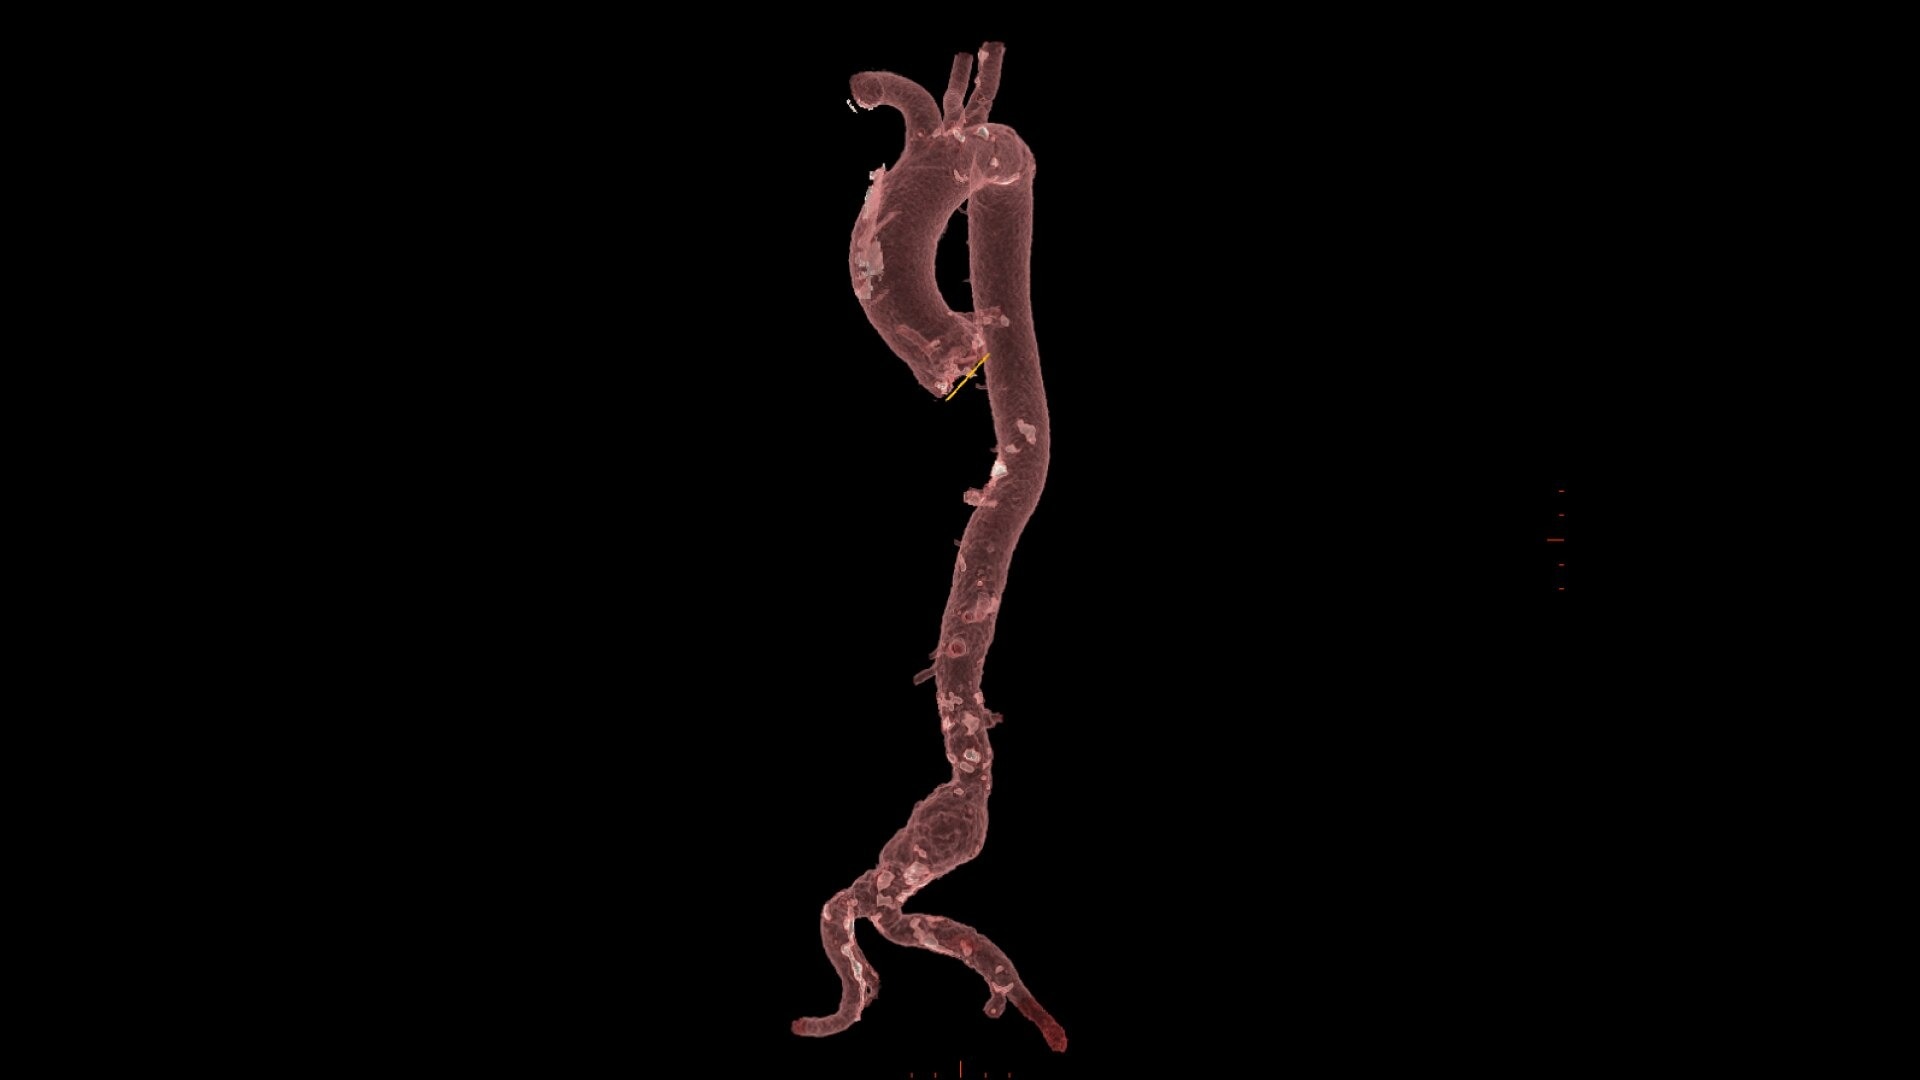

0-click aorta segmentation and valve definition makes accurate valve sizing accessible to anyone.